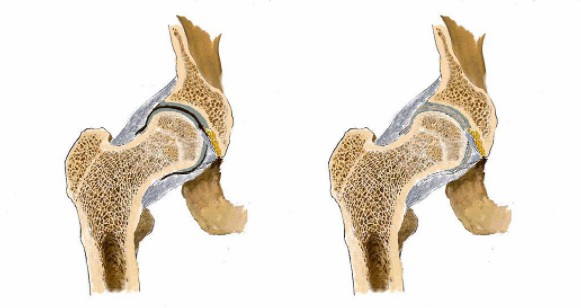

“HLA-B27陰性……從驗血報告來看是正常的……X光……也沒什么問題,這邊建議你再去拍個髖關節的核磁共振。”醫生轉過身對著男孩說。

“這是之前拍的磁共振的片子。”

醫生接過片子對著燈源看了看。

“你這病本來就應該到風濕免疫科來看,你之前去的骨科診斷會不一樣,現在這個片子看不到病痛的地方。”

看男孩不說話,醫生繼續說道:“你的HLA-B27顯示陰性,如果是陽性就可以確診是強直性脊柱炎,現在只能排查……如果確診是強直性脊柱炎,就要就要及早治療,因為這個病是不可逆的,我們只能延緩它病程進度……”